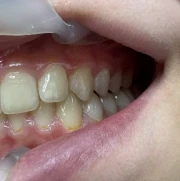

Стрипинг

Serviciul a fost efectuat la Дентално студио ТОП ДЕНТАЛ de томи пелова pe 9 Okt., 25